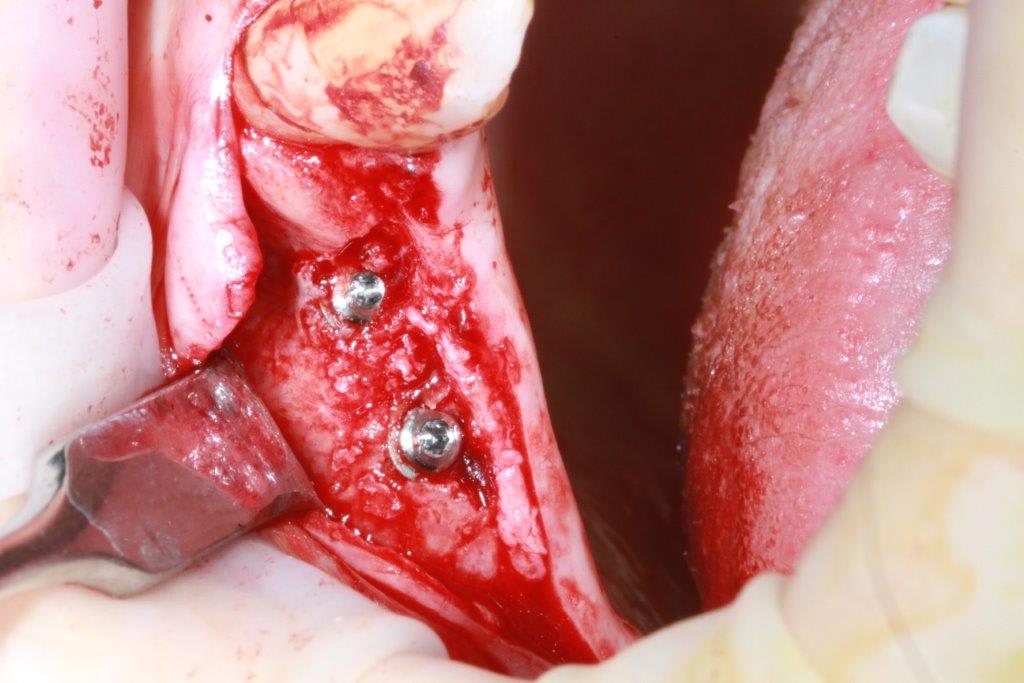

regarde moi ça pxav c'est la suite de mon cas

-> crete de 2 mm , expansion pour mettre du 3.7 sur 13 et 15 + summers dans la même séance sur 15

-> et regarde voir 6 mois après on voit que la 15 s'est légèrement enfoncée sur 2 mm :))))) expansion + summers ça faisait peut être beaucoup.

-> je lui ai posé les vis

-> Et je vais devoir exceptionnellement faire dès pilier CFAO pour corriger très légèrement l'axe (Implants légèrement vestibulés)

Photo 1 expansion plus summers

Photo 2-3 : 6 mois après